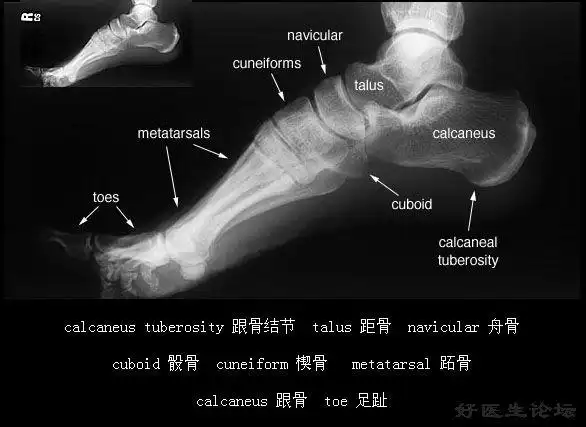

跟骨骨折基础篇

发几张正常x线片